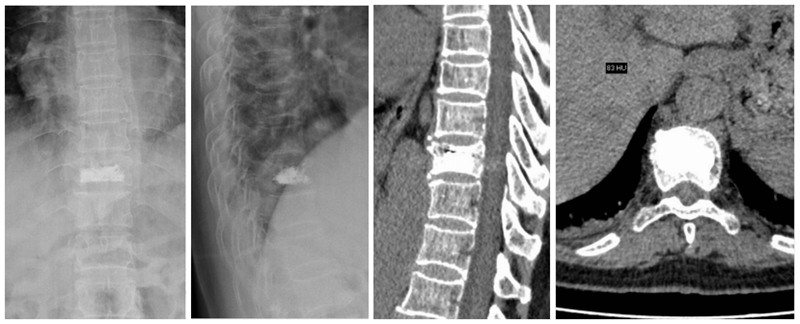

A、B. 术前正、侧位X线片示T10压缩骨折;C. 术前CT矢状位重建示T10压缩骨折;D. 术前MRI抑脂像示T10为新鲜骨折

患者女,73岁,摔伤致T10椎体压缩骨折,伤后3d行PCKP治疗。